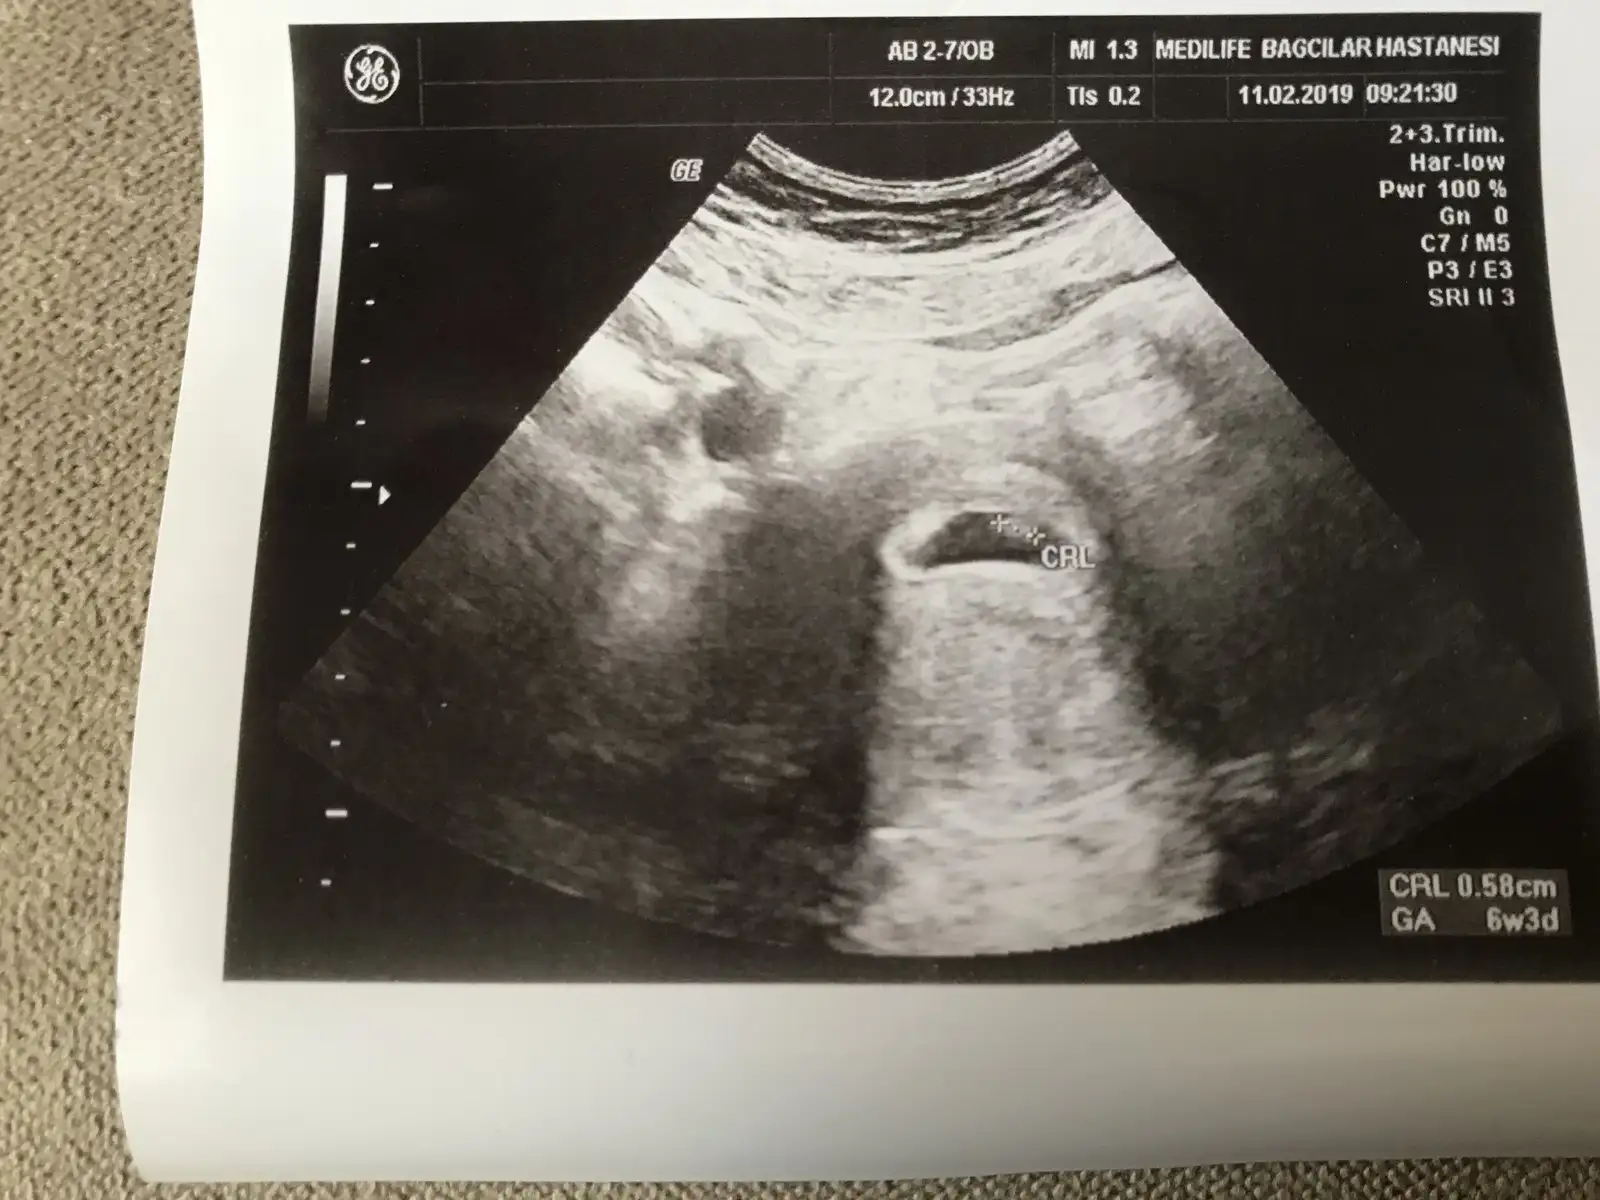

Kızlar bugunden sıcak sıcak 8 haftalık fotoğrafımız bizede bir yorum teyzeleri:anneadayı:

• 20190211_132159.webp

20190211_132159.webp

34 KB · Görüntüleme: 64